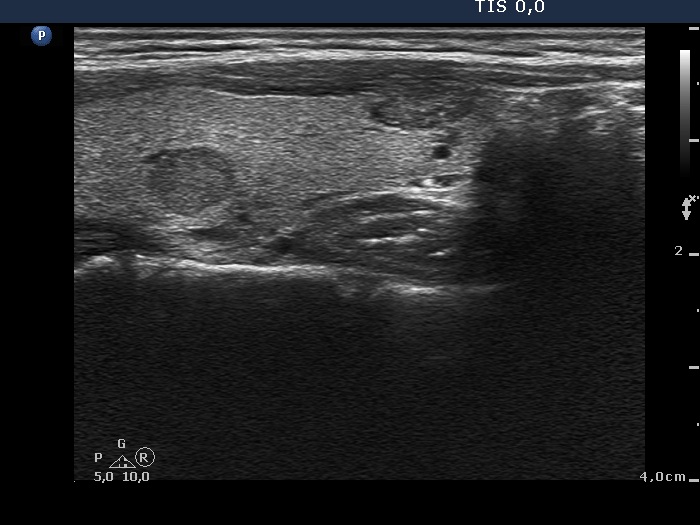

Ultrasonography. The thyroid was echonormal and contained multiple nodules including a hypoechogenic one in the lower pole of the right lobe presenting coarse calcifications. The nodule in the lower part of the left lobe was also noteworthy.

Cytology was performed form the nodule presenting microcalcifications and from that located in the lower pole of the left lobe. The latter resulted in benign colloid goiter while the cytology of the right nodule corresponded to a follicular tumor.